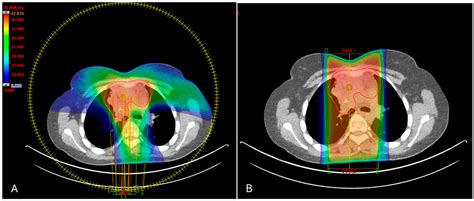

• Radiation Therapy: Depending on the size of the mass and how well it responds to initial chemotherapy, radiation may be used to consolidate the area in the chest to ensure no residual cancer cells remain.